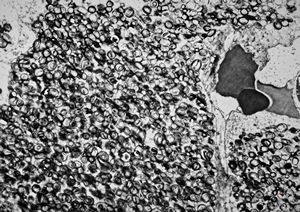

M, 44y. | Gaucher disease … spleen